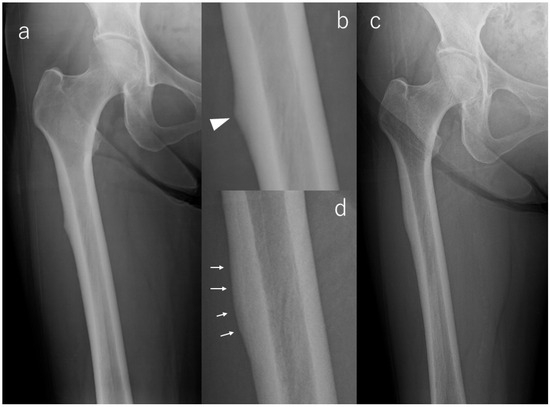

Radiographic Evolution of Contralateral Asymptomatic Incomplete Atypical Femoral Fractures in Autoimmune Disease Patients

Background/Objectives: Atypical femoral fracture (AFF) represents a diagnostic and therapeutic challenge, particularly in autoimmune disease patients receiving long-term bisphosphonate (BP) and glucocorticoid (GC) therapy. Although bilateral AFF is common, the radiographic evolution of asymptomatic incomplete lesions identified at the time of a complete fracture remains insufficiently defined. This study aimed to characterize the natural history and imaging biomarkers associated with progression in this biologically homogeneous high-risk population. Methods: Ten female autoimmune disease patients with complete AFF and asymptomatic incomplete contralateral lesions were retrospectively evaluated over a mean 59 months. Serial radiographs were assessed for cortical beaking, periosteal flaring, and transverse radiolucent lines. All patients discontinued BP therapy postoperatively; teriparatide was administered when tolerated. Results: Six lesions regressed, three remained stable, and one progressed—this progressing case being the only limb with a transverse radiolucent line at baseline. No patient developed symptoms or sustained a complete fracture on the contralateral side. Radiographic remodeling occurred independently of symptoms. BP discontinuation and, when tolerated, teriparatide appeared to contribute to lesion stabilization, although statistical significance was not achieved. Conclusions: In autoimmune patients with severe long-term BP and GC exposure, most asymptomatic incomplete AFF identified at the time of contralateral complete fracture remains stable or improves under conservative management. A transverse radiolucent line is the most decisive imaging biomarker predictive of progression and warrants intensified surveillance or consideration of prophylactic fixation. Larger cohorts are needed to refine risk stratification algorithms and optimize diagnostic and management strategies. Full article

Figure 1